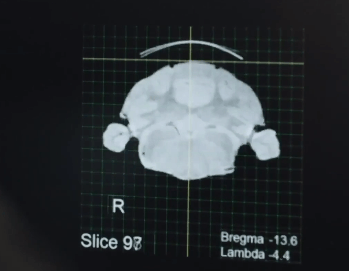

Şirket, 2020’nin ilk haftalarında beyinle bilgisayar arasında iletişim sağlayabilecek bir mikroçipin maymunlar üzerinde test edildiğini ve başarı sağlandığını duyurdu.

Testte beyne bağlanan, saçın dörtte biri genişliğinde 4 elektrot iplik ve onlara bağlı bir çip kullanıldı. Geçtiğimiz ağustos ayında ise işitme cihazı gibi kulak arkasına takılan çip yerine madeni para boyutunda olan ve doğrudan insan beynine bağlanan ara yüz kullanılacağı açıklandı. İlk denemeler ise domuzlarda yapıldı.

İnsan kafatasına robot bir kol ile yerleştirilecek çip, bu elektrot ipliklerle beyindeki ilgili noktalara bağlanacak. Dışardan görünen hiçbir şey olmayacak.